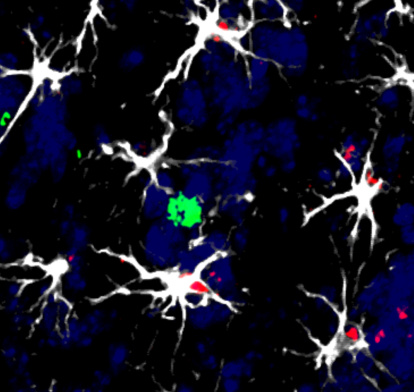

Células en torno a una metástasis cerebral en modelo animal: varias células cerebrales (astrocitos, blancas) rodean a una célula del sistema inmunitario (linfocito, verde). Algunos de ellos han empezado a activar el factor (rojo) inductor de la molécula TIMP1, que les permitirá inhabilitar la acción del linfocito contra las células tumorales